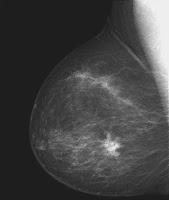

A presidente da Fundação Laço Rosa, uma das entidades promotoras do evento, Marcelle Medeiros, diz que a estimativa é que 57 mil novos casos devem ser diagnosticados no Brasil este ano. Segundo ela, a campanha Outubro Rosa, que tem ações no Brasil desde 2002, ajudou a tornar o assunto mais conhecido e discutido.

A presidente da Fundação Laço Rosa lembra que não existe prevenção contra o câncer de mama, mas a detecção precoce pode fazer a diferença entre a vida e a morte da paciente. A enfermeira Vania dos Santos Maia foi diagnosticada com a doença em 2010 ainda no início. Se submeteu à quimioterapia, mastectomia e radioterapia e teve metástase dois anos e meio depois do diagnóstico. Atualmente faz tratamento para controle da doença. Para ela, é fundamental o apoio das instituições de combater ao câncer.